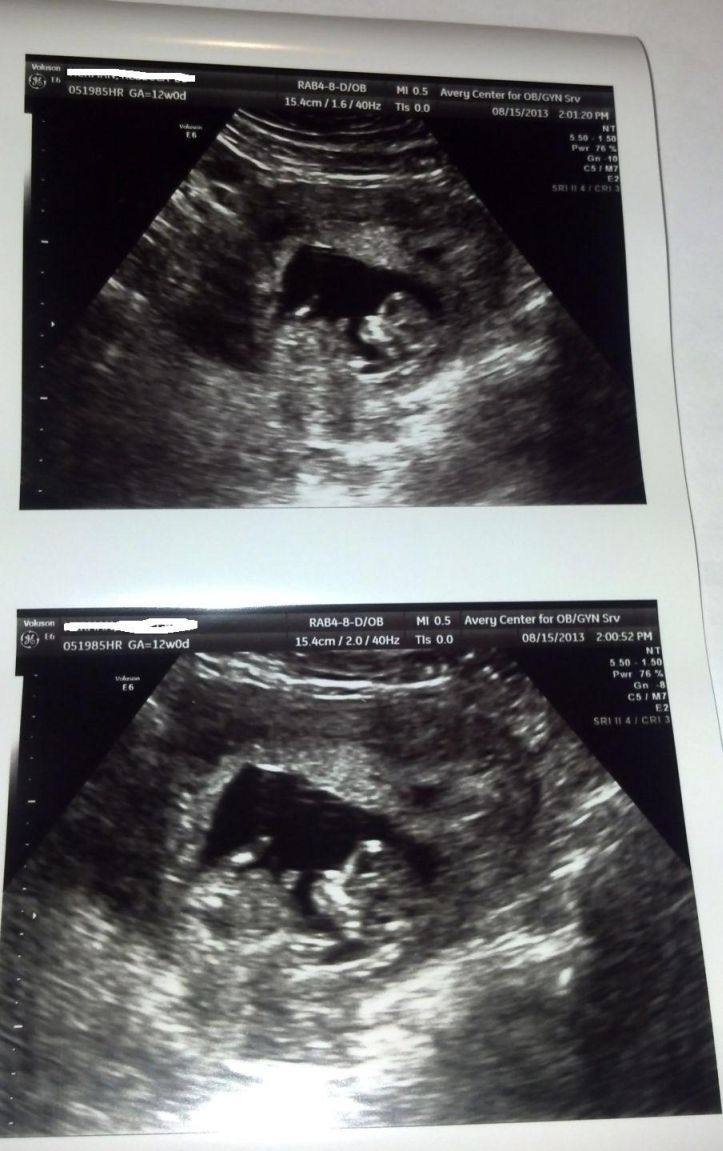

I did PGD for a girl, but for some reason I am so nervous about an opposite. These were taken today at 12w0d. The baby was moving around a lot, and I'm not sure if any of these even show a nub:

Attachment 13150